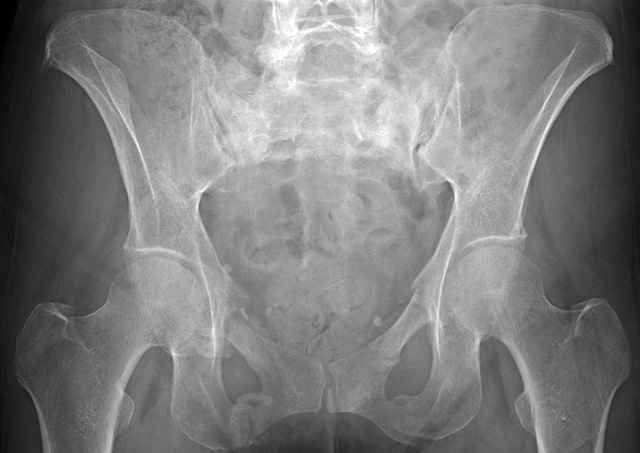

3 Months After Fall

Continued Pain & Immobility

(+) Instability to Compressive Manual Exam

Pelvic CT Scan - 3 Months After Fall

Sacral Injuries

Ramus Fractures